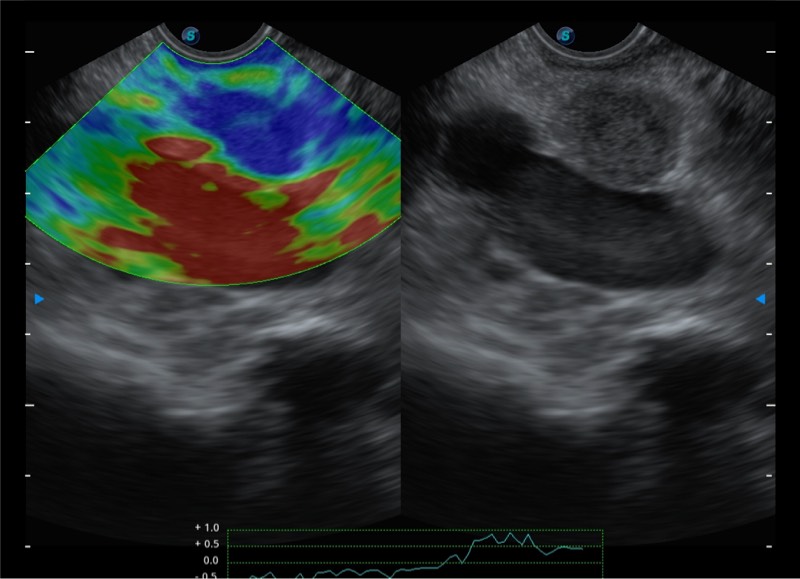

基于二十年的超声技术积累,美狮贵宾会官网提供了最新一代的独立超声主机,在提供高质量图像的同时满足多学科使用。具备常见多普勒技术并提供弹性成像、声学造影等高端影像技术。新一代传感器具有更强的抗干扰能力并减少图像伪影。